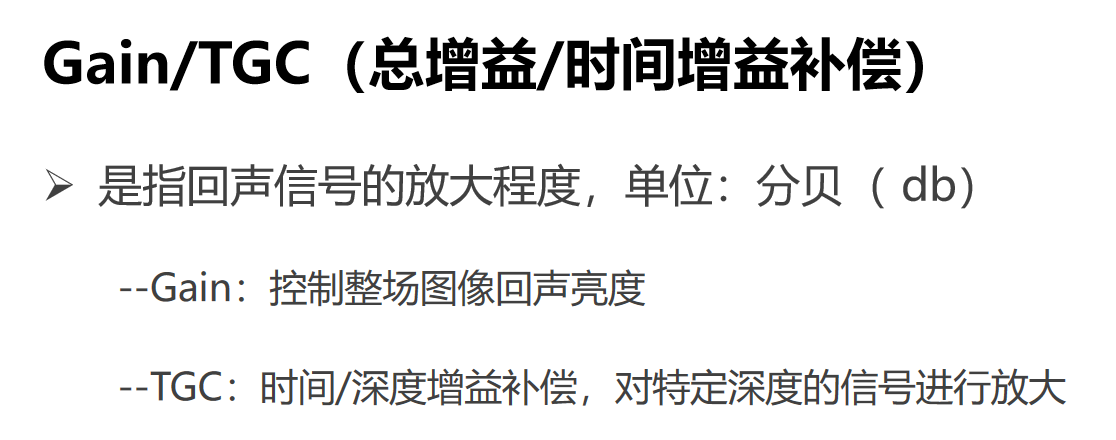

Gain是图像的总增益,是控制整场图像回声的亮度,增加增益使图像亮度增加,可以观察到更多回声信号,但同时也会带来更多噪声。

TGC时间增益补偿,是对特定深度的信号进行放大,分段调节增益。一般采用近场抑制,以减弱接近探头部位组织内过强回声光点;远场提升,以补偿远场组织回声的明显衰减。总的原则是,使不同深度的图像,亮度显示均匀一致。

这幅图像就是增益过高,图像亮度太亮,得到回声信号很多,但同时也有很多噪声。经过降低增益就会得到这幅质量很好的图像。